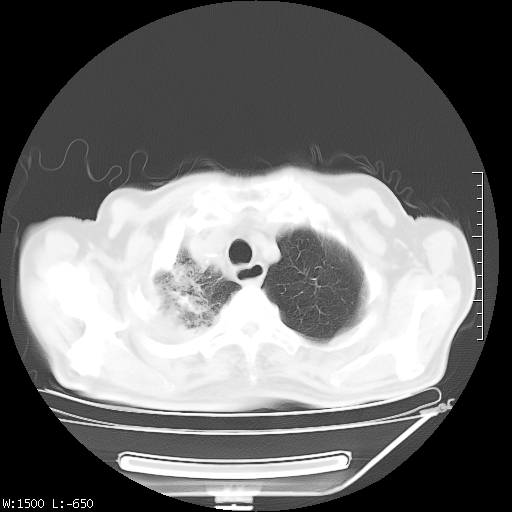

标题: CT23994:男、72、咳嗽、气短两月余,近来消瘦。 [打印本页]

标题: CT23994:男、72、咳嗽、气短两月余,近来消瘦。

右上肺实变,与胸膜关系密切,右肺容积缩小,隆突下淋巴结增大,考虑1 肺结核 2 肺癌

右上肺大片状密度增高影,与胸膜关系密切,内见低密度透亮影,胸膜下可见三角形不张影,左下肺沿支气管走形结节影,纵膈内淋巴结显示。考虑结核并疤痕性不张可能性大,建议穿刺活检,排除肺泡癌。